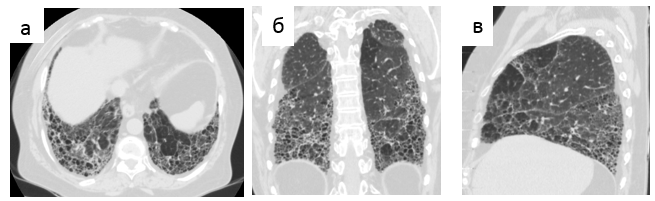

- периферические тракционные бронхо- или бронхиолоэктазы [42] (Рис. 1-3).

Рис. 2. Обычная интерстициальная пневмония, типичная картина. Сотовое легкое на аксиальном срезе (а), при реформации во фронтальной (б) и сагиттальной (в) плоскостях.